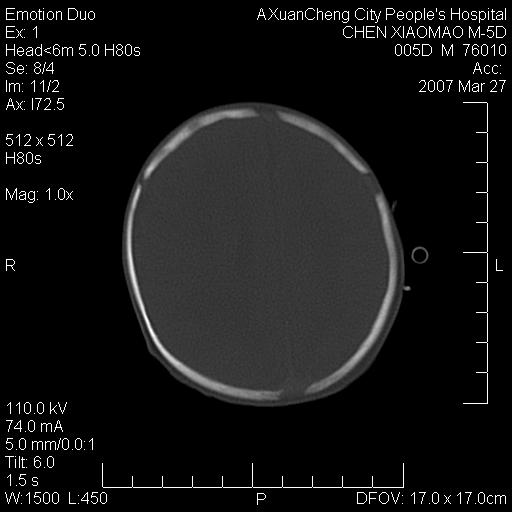

大家看看可有出血?另外枕骨中央是骨缝还是骨折

颅内未见明显异常。枕骨鳞部应为假缝(颅外软组织无肿胀),有外伤吗?

枕骨骨折可以下,应该比较明显,颅内还是正常的,不放心的话,短期随访。